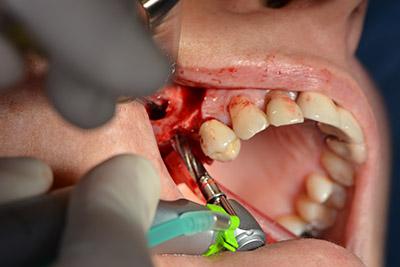

Procedimiento quirúrgico durante el implante

Imagen 9: Visión global y ajuste para el fresado piloto.

El guiado clásico del corte (crestal, descarga bucal) y la preparación del colgajo mucoperióstico permiten obtener una buena visión global.

En este caso se utilizan implantes Sky (Bredent), cuyo protocolo quirúrgico exige el fresado piloto a unas 1.200 rpm (figura 9).